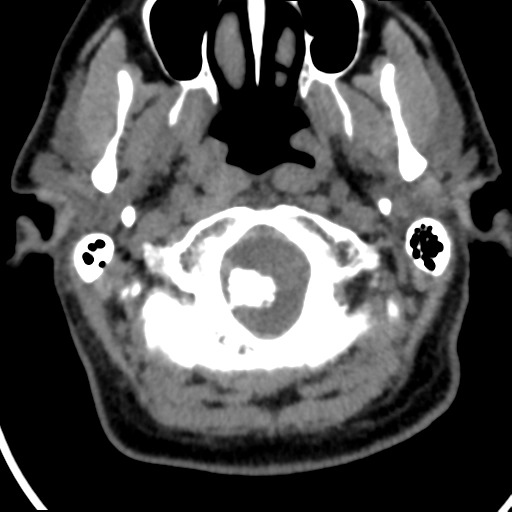

Phân loại Koos cho u schwannoma tiền đình - Koos classification of vestibular schwannomas